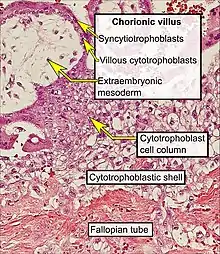

- Floating villi float freely in the intervillous space. They exhibit a bi-layered epithelium consisting of cytotrophoblasts with overlaying syncytium (syncytiotrophoblast).

The bulk of the villi consist of connective tissues that contain blood vessels. Most of the cells in the connective tissue core of the villi are fibroblasts. Macrophages known as Hofbauer cells are also present.

Micrograph showing chorionic villi. Intermediate magnification. H&E stain.

Micrograph showing chorionic villi. Intermediate magnification. H&E stain. Micrograph showing chorionic villi. Very high magnification. H&E stain.